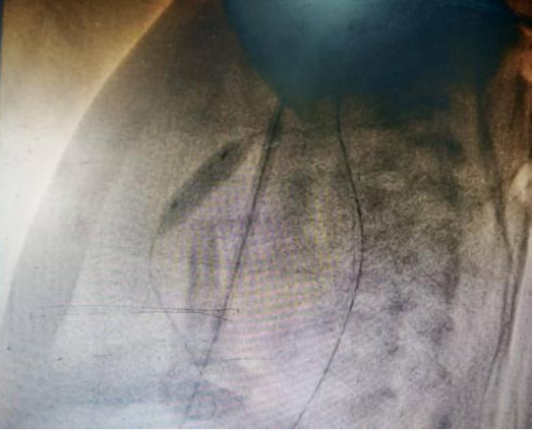

图中为肺动脉球囊扩张即刻,狭窄腰征消失,达到有效扩张

手术室内,麻醉团队为手术精准护航,新生儿科刘红副主任医师全程严密监护生命体征,守住安全底线。小儿心脏科张庆彪主任团队在影像引导下,凭借高超技术,仅依靠一根微导丝建立轨道,成功将球囊导管送至狭窄的肺动脉瓣处。随着球囊的扩张,原本近乎闭锁的瓣膜被成功打开。术后即时测量显示,跨瓣压差从术前的127mmHg大幅降至12mmHg,患儿血氧饱和度随即显著改善,手术宣告成功。